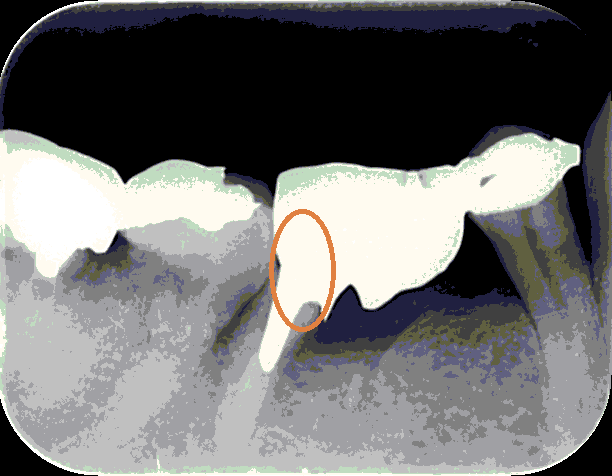

さてこの写真を見てください。

神経をとってかぶせをしているのですが、歯牙は神経をとるとその時点から本来の強度を失い始め、10年の経過を超えるあたりから破折を起こすことがよくあります。

この状態では、おそらく抜歯を提案されることでしょう。

オレンジの丸の部分が今回割れて抜歯となりました。